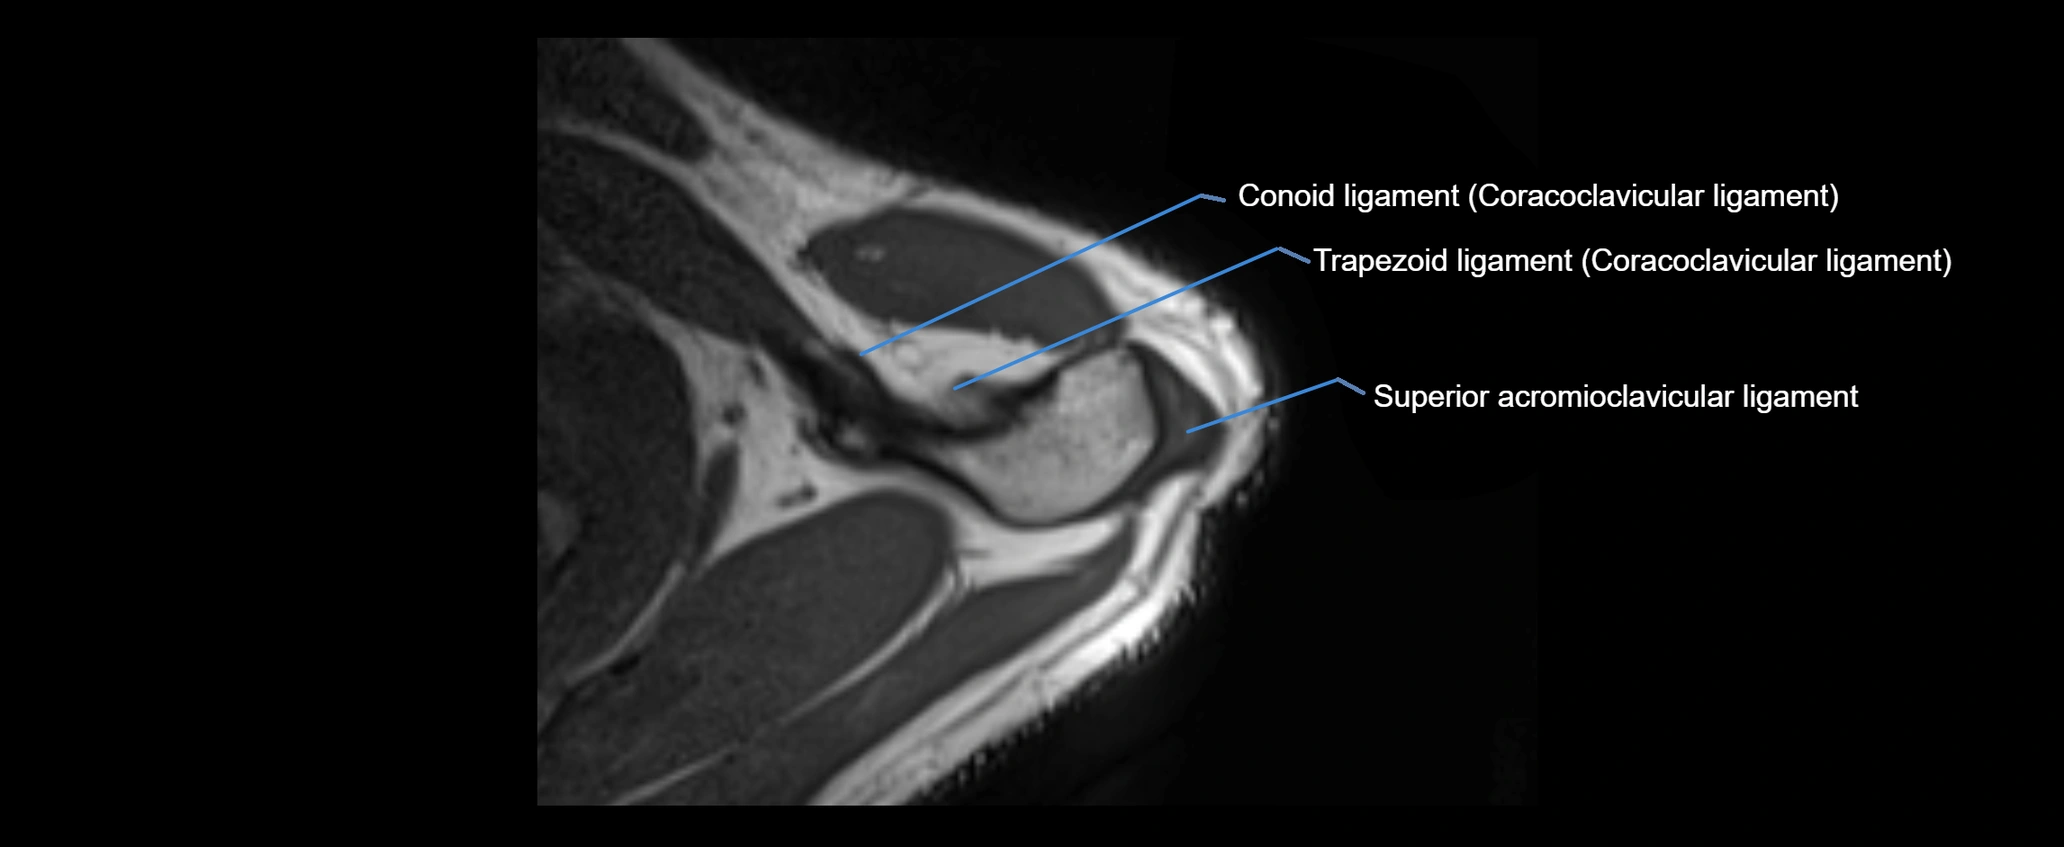

CT image

image